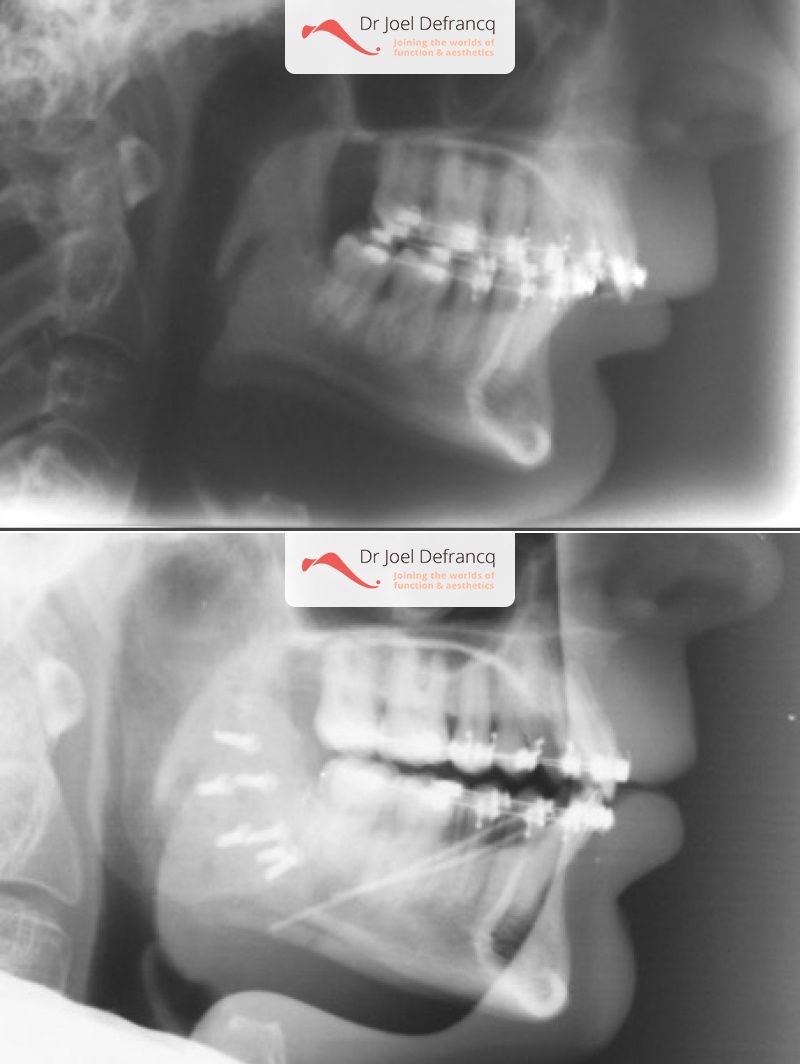

Kaakchirurgie

- Verlenging onderkaak (BSSO)